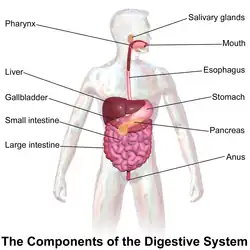

Gastrointestinal diseases (abbrev. GI diseases or GI illnesses) refer to diseases involving the gastrointestinal tract, namely the esophagus, stomach, small intestine, large intestine and rectum, and the accessory organs of digestion, the liver, gallbladder, and pancreas.